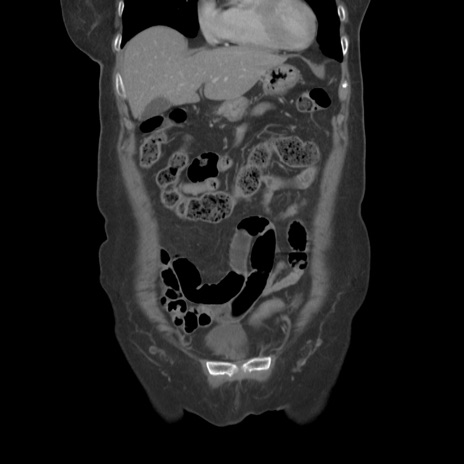

症例19(冠状断像)

【症例】80歳代女性

【主訴】下腹部痛

【現病歴】約8時間前より下腹部痛の出現あり、救急外来受診。

【既往歴】両側付属器切除

【身体所見】意識清明、下腹部正中に手術痕あり、その部位に一致して圧痛と反跳痛あり。腸蠕動音は亢進。

【データ】WBC 9300、CRP 0.15